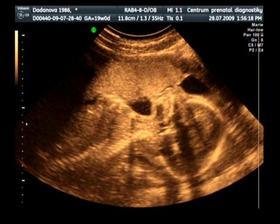

Naše maličké

Dne 15. 12. v 5:40 se nám narodil syn Jurášek. Vážil krásných 3500g a měřil ukázkových 50 cm. A je to nejkrásnější kluk na světě : )